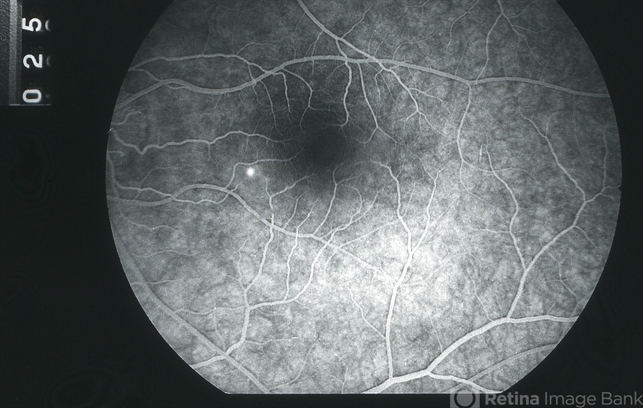

- central serous retinopathy (CSR), fluorescein angiogram (FA), fluorescein leakage, FA mid phase

- 32 year old white female with acute CSR OS; early venous filling phase of FA showing a pinpoint leak in inferonasal macula; VA = 20/30-2.